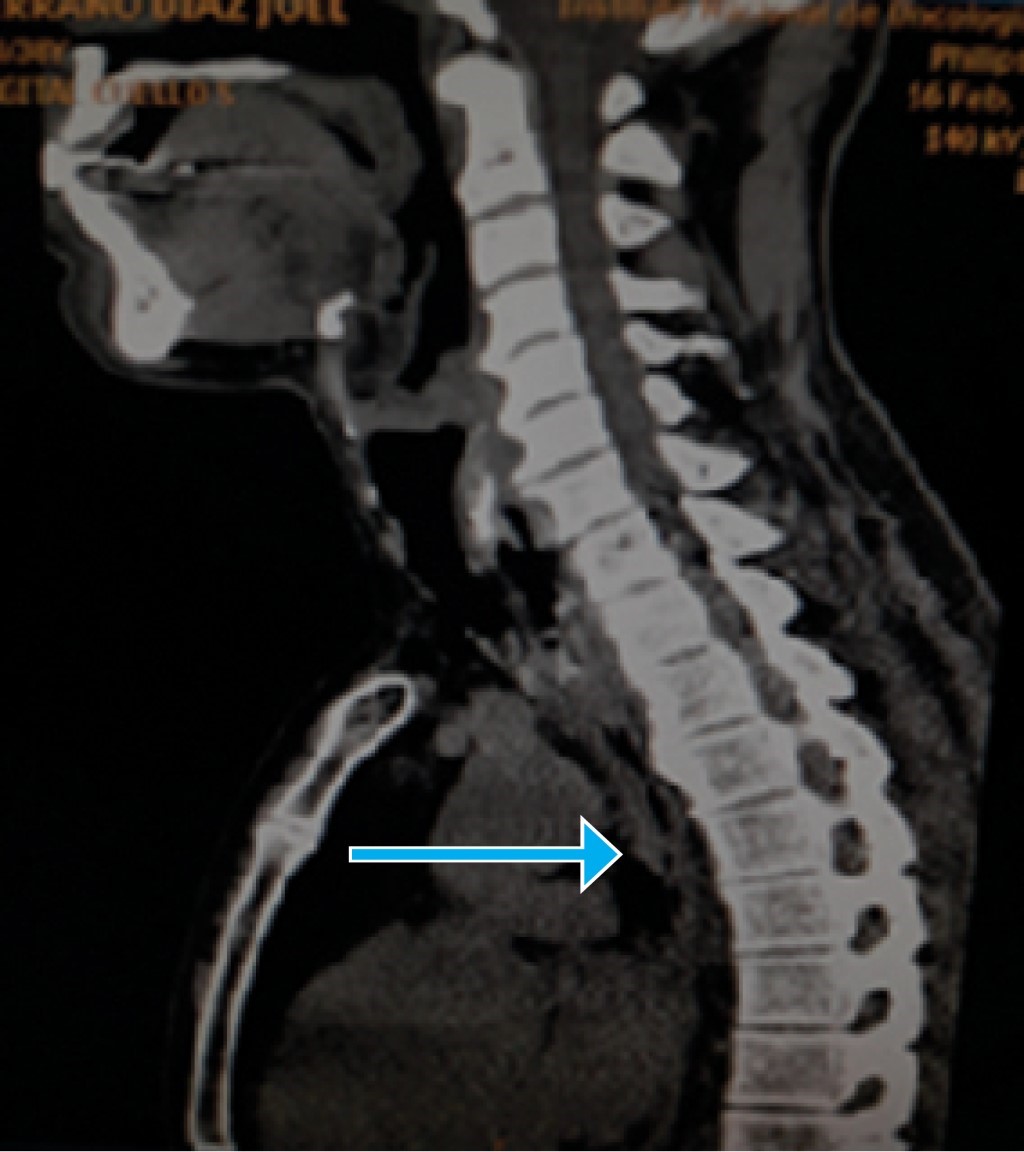

CT scan with contrast, with 2 and 5 mm cuts, showed a high-density image of 56 UH in the neck, of 17 mm in length, between the cervical esophagus and the cricoid cartilage, suggestive of a foreign body. Above it, the esophagus had very thick walls of 20 mm, through an approximate length of 30 mm, causing stenosis and compression of the trachea, thickening of soft tissue at T1 and T2 adjacent to the described lesion, pre-tracheal adenopathy of 8 mm, and osteo-degenerative changes (Figure 2).

Figure 2